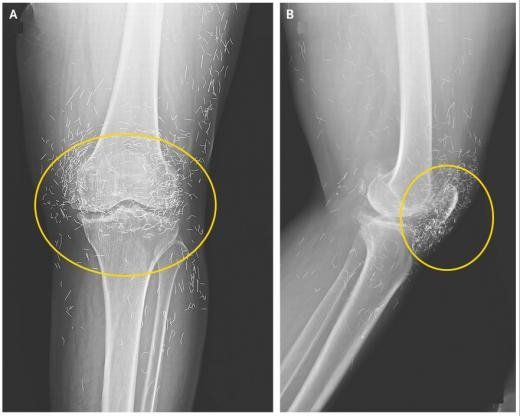

국제 학술지인 ‘뉴잉글랜드 의학 저널’에 나온 65세 한국 여성의 무릎 엑스레이 사진. 뉴잉글랜드 의학 저널 캡처 |

2014년 임상 의료분야 국제 학술지 ‘뉴잉글랜드 의학 저널’에 65세 한국 여성의 무릎 엑스레이 사진이 실려 금침시술에 대한 위험성을 강조하기도 했다.

해당 여성은 퇴행성 관절염이 낫지 않자 통증 완화를 위해 ‘금침 요법’을 받았다. 통증 완화를 위해 계속 침을 주입하다 보니 무릎에 박힌 침의 개수가 수백 개가 넘었다.

미국 보스턴대학 방사선과 알리 게르마지 교수는 “신체는 이물질이 들어오면 이를 제거하려는 방어 작용을 수행하기에 해당 과정에서 염증 등이 발생할 수 있다”며 “또한 침들이 몸속을 돌아다니면서 동맥과 같은 중요 부위를 손상시킬 수도 있다”고 우려했다.